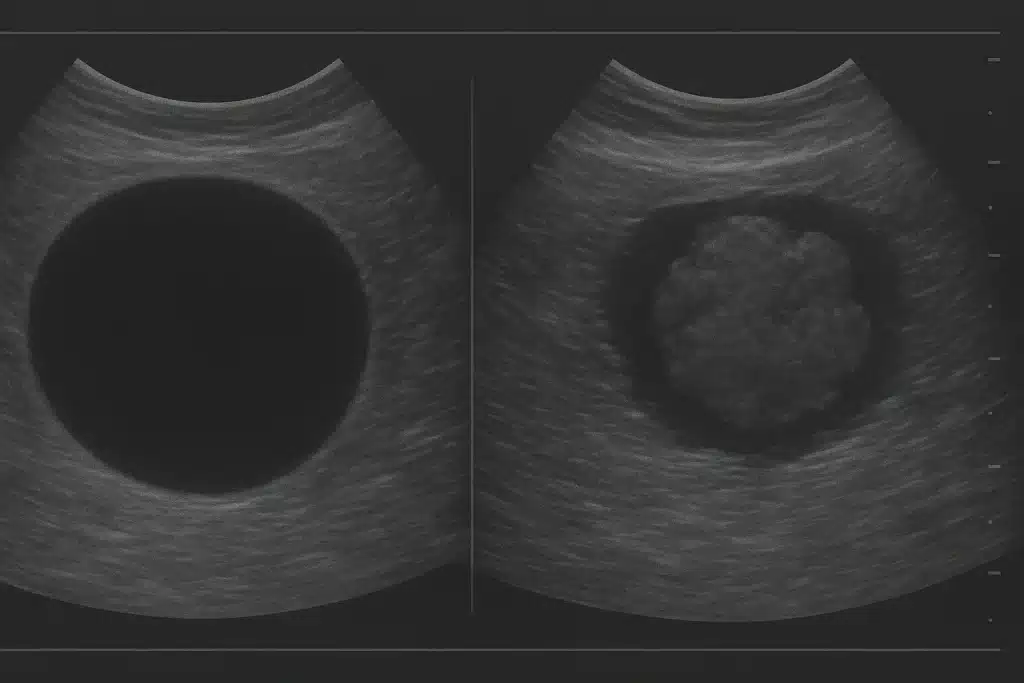

اولین اقدام معمول برای بررسی ماهیت تودهها انجام تصویربرداری است. سونوگرافی (اولتراسوند) یک روش متداول و بیخطر است که میتواند نشان دهد توده حاوی مایع است یا جامد. سونوگرافی بر اساس امواج صوتی کار میکند و کیست (به دلیل محتوای مایع) را از تومور جامد متمایز میکند. اگر توده کیستیک باشد (یعنی روی سونوگرافی کاملاً سیاه و یکنواخت دیده شود که نشاندهنده مایع است)، احتمال خوشخیم بودن آن بسیار زیاد است.

در مقابل، اگر درون کیست اجزاء جامد مشاهده شود یا توده کاملاً جامد باشد، نیاز به بررسی بیشتر دارد زیرا ممکن است بدخیم باشد. علاوه بر سونوگرافی، سیتی اسکن (CT) و امآرآی نیز برای بررسی دقیقتر برخی تودهها بهکار میروند و تصاویر مقطعی از داخل بدن فراهم میکنند. این روشها مخصوصاً در بررسی تودههای عمقی یا اندامهای داخلی (مثل کبد، مغز و غیره) مفیدند. برای بررسی تودههای پستان از ماموگرافی (تصویر پرتوی ایکس از پستان) نیز استفاده میشود. تصاویر ماموگرافی یا سونوگرافی پستان میتواند نشان دهد توده مشکوک کیست ساده است یا نه.